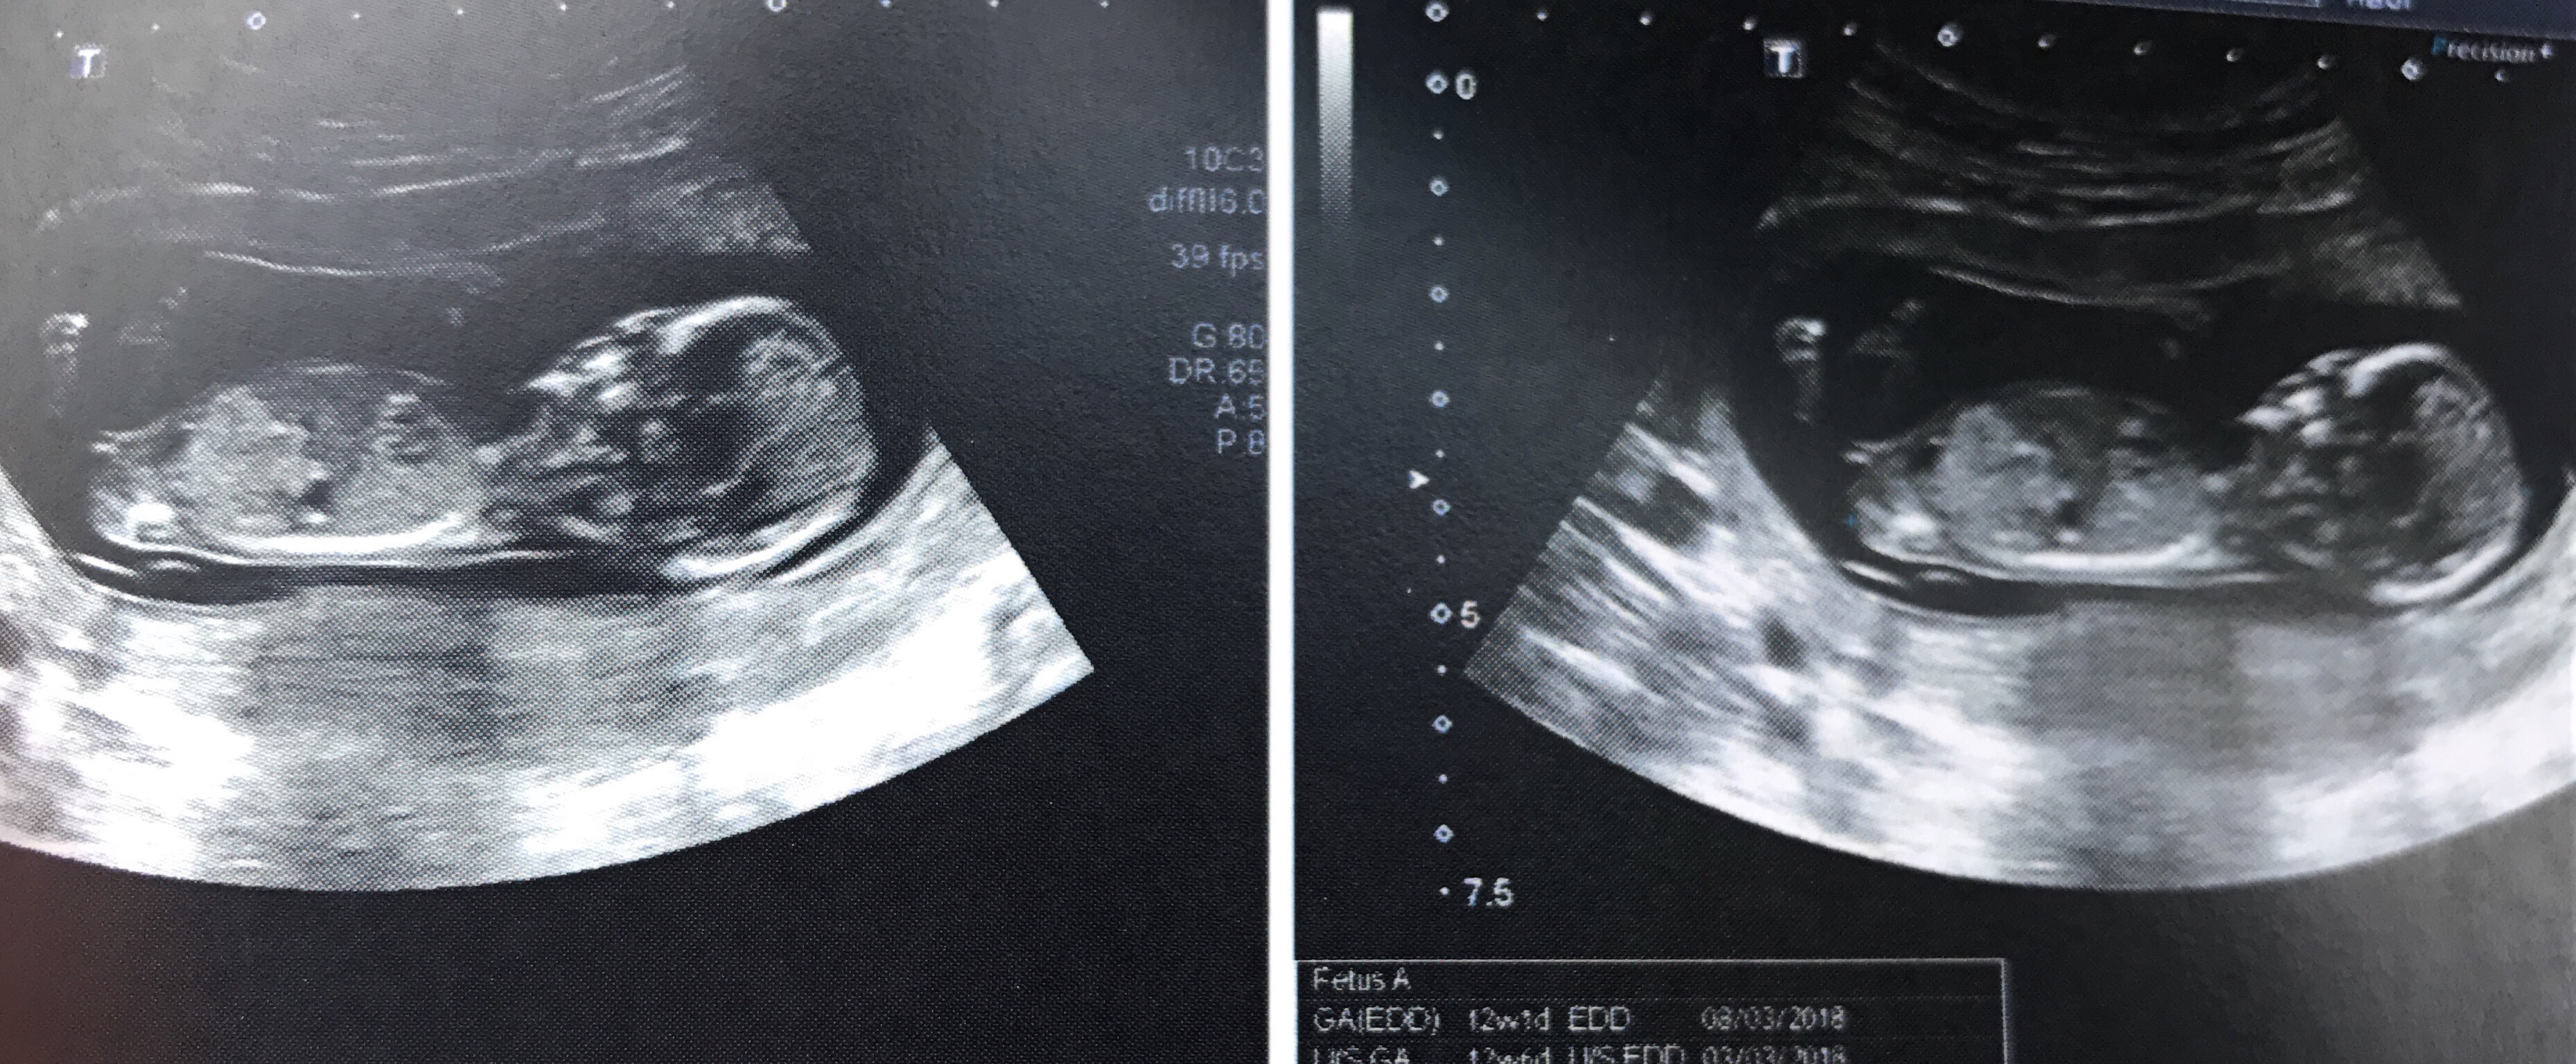

I'm 12+1 by my dating scan but 12+5 according to measurements in this scan. Attachment 37450